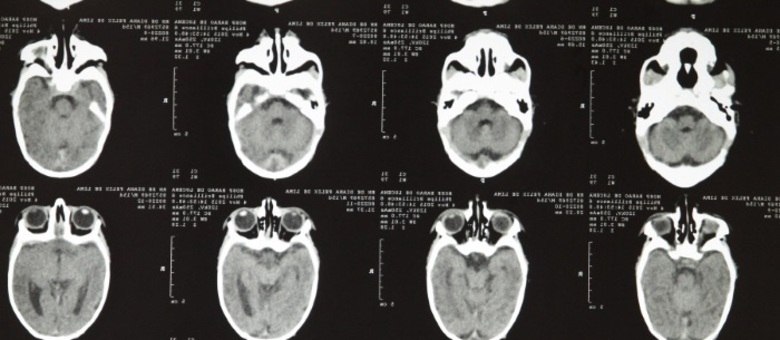

Brasil vive surto de microcefalia EDMAR MELO/JC IMAGEM/ESTADÃO CONTEÚDO